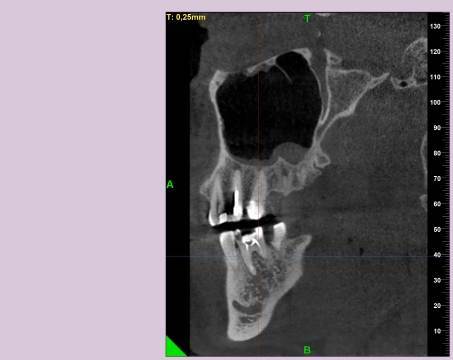

КТ от 28.05.2024

28_05.24(2).jpg.0ffa1febe861106733e1de830afbe6f4.jpg28_05.24-1(2).jpg.9c45d7be16aeed505bd413ce9bc6e69e.jpg28_05.24-2.jpg.a728a7d7e6213c1c8302b43adc89e4d0.jpg28_05.24-4(2).jpg.ac43f3448a3988c7006f74e1d0ce09da.jpg28_05.24-6(2).jpg.dd1fd85c6cc0fcd3d43bd9e71fc0d616.jpg28_05.24-8(2).jpg.885c8cb905445e9308f124fb9e5c616b.jpg28_05.24-9(2).jpg.6cceaaaa1b56d0967482c87b951fbe2d.jpg28.5.24-5(2).jpg.b2d79427a16769c9fd4f0d0911a9db8f.jpg28.5.24-7(2).jpg.f6c17f9820e72dc2708955a65a190b57.jpg28.0524-3(2).jpg.0aa9f153071766a340b428158a94ade8.jpg